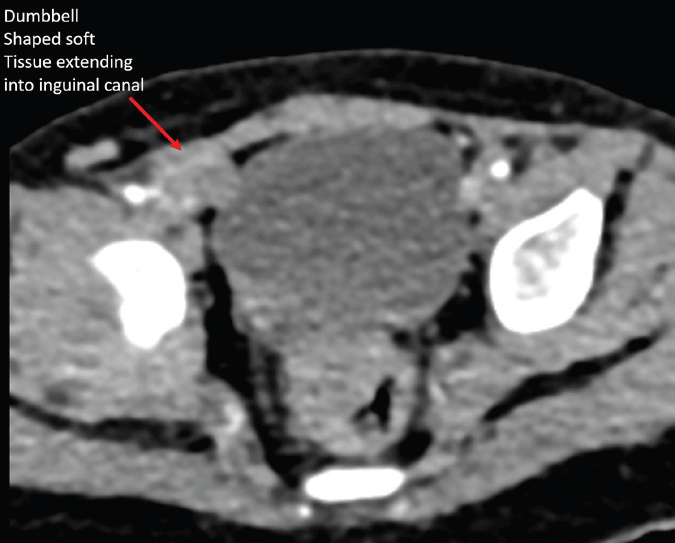

failed to identify the left testis. Contrast-enhanced CT (CECT) pelvis

revealed a dumbbell-shaped enhancing soft tissue density extending

from the right inguinal canal into the scrotum [Figure 1,2,3].

Figure 2: Oblique sagittal reconstruction of CECT pelvis demonstrating

dumbbell-shaped soft tissue density in the inguinal ring tracking into the right

scrotum.